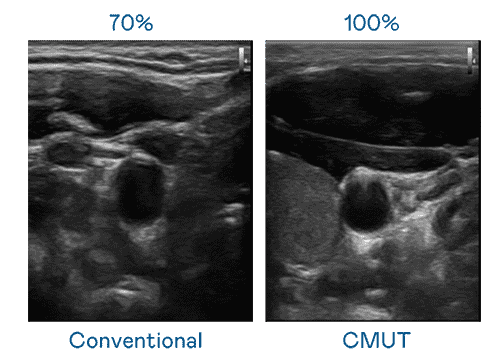

CMUT 技术是一种用电容式微机电元件来产生超音波讯号的技术。。与传统 PZT 压电式技术相比,,CMUT 频宽增加 30%,,,更宽频的超音波讯号让影像解析度大幅提升,,,,是实现高影像品质医疗超音波扫描、、、、促进精准医疗发展的关键技术。。

大频宽带来超清晰影像

超音波影像的解析度高低,,,首先取决于探头能发出的讯号频宽。。。尊龙集团 CMUT 可提供高清晰的超音波讯号,,,提供高频宽、、高灵敏度、、、、影像纹理细节更高的超音波影像,,,协助医护人员缩短影像判读时间及利用精准的医疗影像进行诊断。。